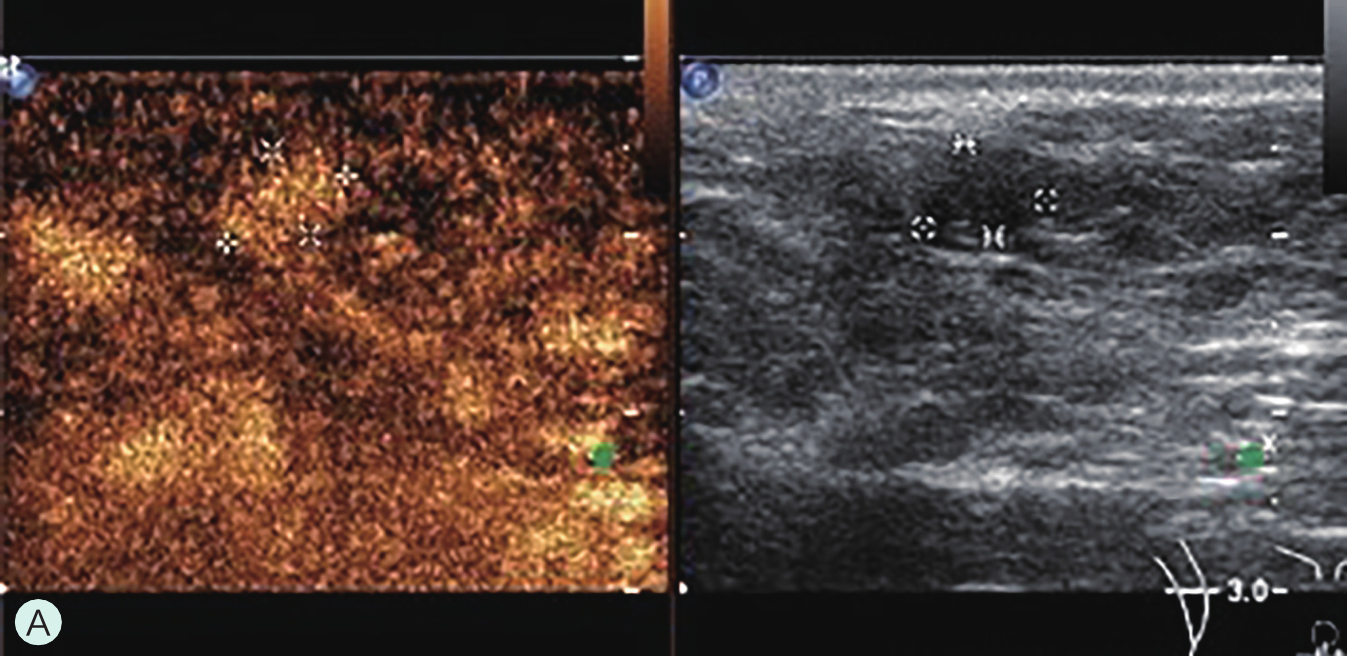

图2-2-1 确定造影病灶

A.病灶二维图像;B、C.病灶CDFI图像;D.同侧腋窝淋巴结情况;E.病灶弹性成像图像